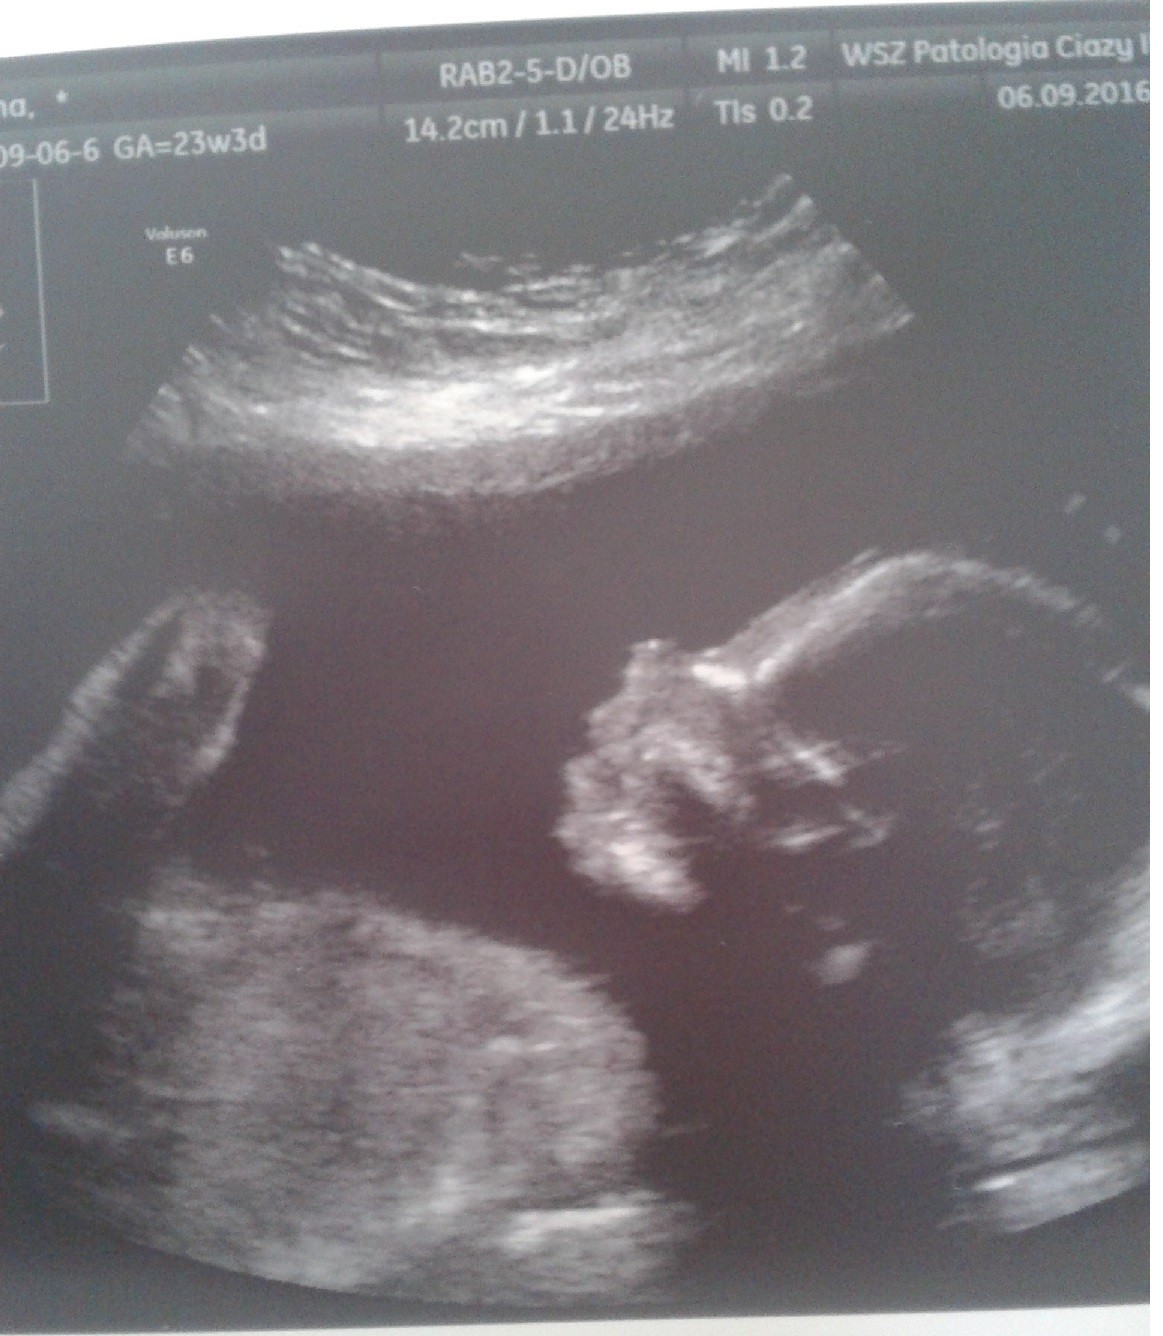

hej, u mnie wariackich papierów ciąg dalszy, zaraz lece na prenatalne. Na szczęście nie boje się ich tak jak poprzednio. W szpitalu dopiero co robiono mi usg i wszystko jest ok. Przedstawiam Wam Nikodema :) całe 600g wagi :)

• 20160906_134456.jpg

310,2 KB · Wyświetleń: 398